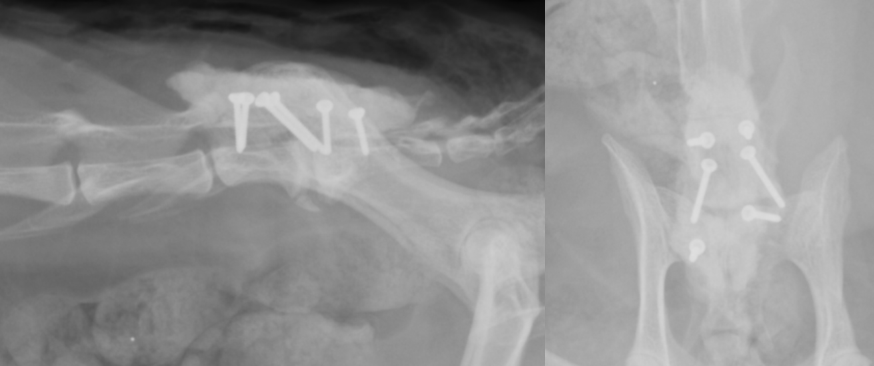

L7とS1(第7腰椎と仙骨)の部分での神経圧迫が確認できました。治療には内科的に痛みを取る方法や、外科治療がありますが根本を解決するには現在のところ外科治療しかありません。 手術では背中からアプローチし、骨と靭帯を除去したのちに腹側の圧迫があればそれも除去します(減圧)。その後に腰を曲げ伸ばした状態でスクリューと骨セメントを利用して固定します。

斜めに入っているスクリュー2本が経関節固定のスクリューで、他の4本は骨セメント固定用のスクリューです。スクリューのヘッドを覆っているものが骨セメントです。

真ん中の2つが経関節固定のスクリューで、前後2本ずつ入っているのが骨セメント用スクリューです。それを覆う四角形のものが骨セメントです。スクリューにはロッキングスクリューを利用しています。 術後は神経の再生を促すためにリハビリを行います。術後しばらくすると痛みが取れ、少しずつ麻痺などが良化していきます。

スクリューとセメントで固定されています。